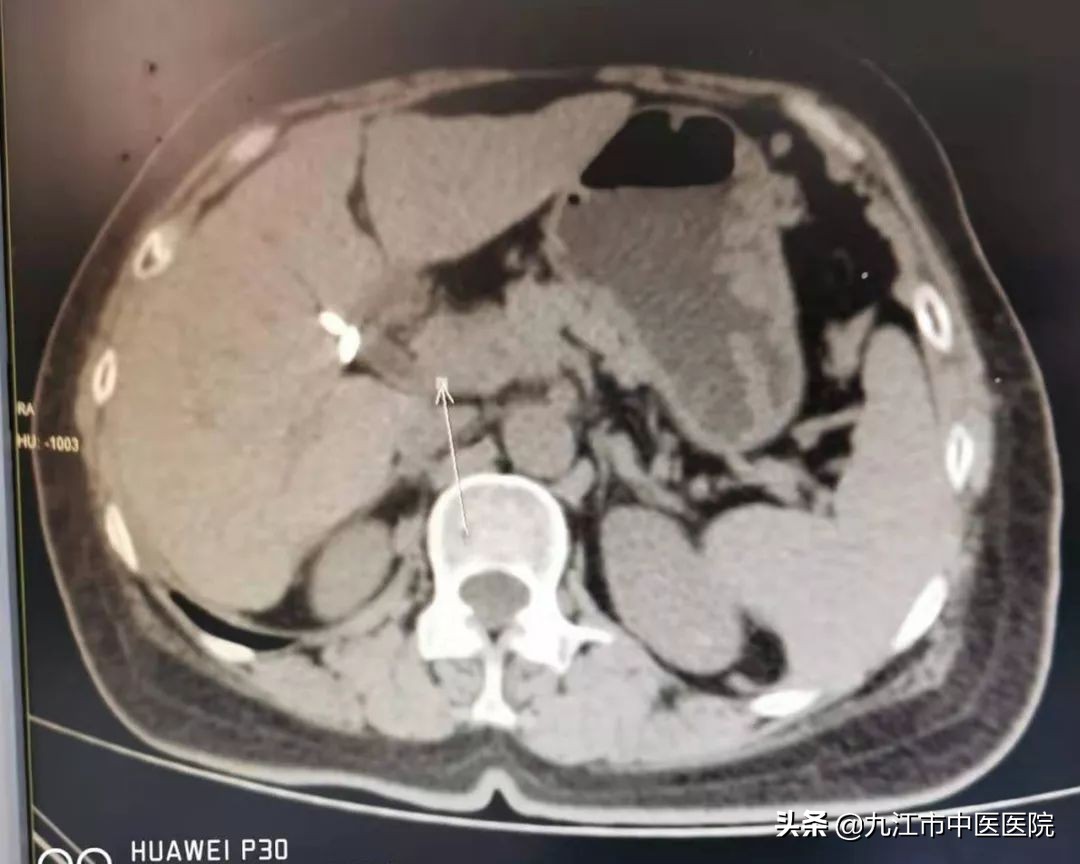

在经过9个月的精心治疗,该病友胰腺内肿块基本消失,肝脏最大占位也从29mm缩小至6mm,肿瘤标志物CA199从3万多降至正常范围,患者现无明显不适。

胰腺治疗后